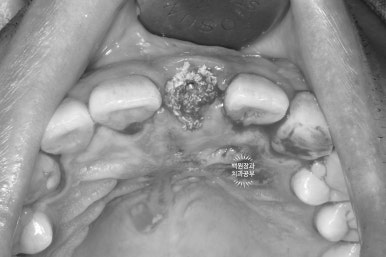

40대 남자 환자분이셨고, 처음 뵈었을 때 왼쪽 위 대문니가 이미 부러진 상태로 오셨었어요.

입천장 쪽에서 바라보았을 때, 이미 잇몸라인보다 깊은곳까지 부러져 있는 뿌리만 남은 치아를 보실 수 있어요.

예전에 신경치료를 해놓은 치아라 앞니 뿌리가 이미 검게 변해버린 상태입니다.